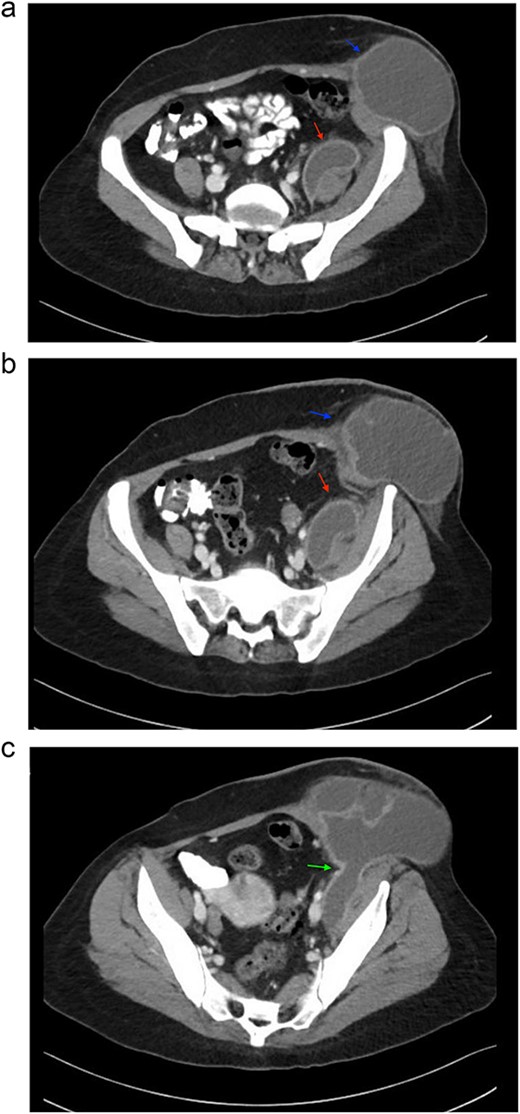

The patient was admitted for further evaluation and management. Correlating her clinical history and physical examination findings with imaging studies, a CT scan of the abdomen revealed a 17 × 8 × 7 cm (transverse × craniocaudal × anteroposterior) multiloculated iliopsoas abscess tracking along the left inguinal canal, accompanied by destruction of the third and fourth lumbar vertebrae suggestive of a pyogenic etiology. Based on these findings, a diagnosis of Tuberculous spondylitis (Pott’s disease) with a secondary psoas abscess was made. Other nearby structures appeared unremarkable on imaging. Three sequential images of CT with contrast from the abdomen and pelvis series are provided, illustrating the pathology in detail (Fig. 1a–c).

Sequential images of CT with contrast of the abdomen and pelvis demonstrating the pathology. (a) Slice 96—a small fluid collection in the left psoas muscle (lower arrow), and a low-density fluid collection in the left inguinal region (upper arrow), both with wall enhancement, consistent with abscess formation. (b) Slice 102—progression and enlargement of the iliopsoas (lower arrow) and inguinal (upper arrow) abscesses. (c) Slice 110—connection between the iliopsoas and inguinal abscesses, indicating advanced spread of infection (arrow).